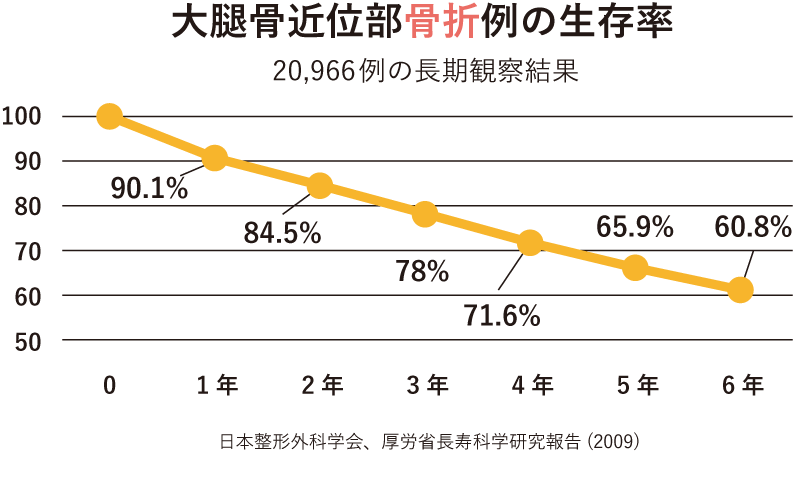

骨折と生存率

ご高齢の患者さまは、骨粗鬆症等により軽度の転倒などでも骨折する場合があります。一度骨折すると再骨折する可能性が高まり、脆弱性骨折により健康度が悪化します。なかでも大腿骨近位部骨折や椎体骨折は、以前の健康状態に回復することは困難になります。また、骨折後の死亡率が高くなるデータが確認されています。

下の図は、大腿骨近位部骨折をすると6年の間に40%近くの患者さまが亡くなっていることを示しています。

これらの報告は、骨折による活動性の低下から嚥下機能を含む筋力低下・環境の変化による認知症の発症や増悪・せん妄が出現する可能性があることや、心不全・肺・脳血管障害・全身の感染症などにより命を脅かす合併症を起こす可能性があることを示しています。早期手術が予後にはよいと知られていることから、当院では早期に手術を行うことに積極的に取り組んでおります。